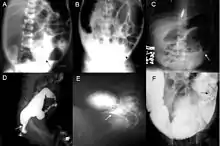

Definitive diagnosis is made by suction biopsy of the distally narrowed segment.[26] A histologic examination of the tissue would show a lack of ganglionic nerve cells. Diagnostic techniques involve anorectal manometry,[27] barium enema, and rectal biopsy. The suction rectal biopsy is considered the current international gold standard in the diagnosis of Hirschsprung's disease.[28]

Radiologic findings may also assist with diagnosis.[29] Cineanography (fluoroscopy of contrast medium passing anorectal region) assists in determining the level of the affected intestines.